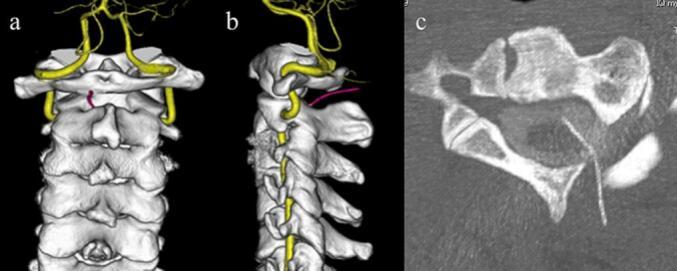

A 37-year-old man presented with neck pain and gait disturbance.While he was self-acupuncturing, an acupuncture needle accidentally broke, and the remaining part of the needle penetrated and made contact with the cervical spinal cord. Cervical spine radiographs showed a metallic foreign body between the C1 and C2 spinous processes in the direction of the anterior cervical spine. Computed tomography images revealed that the acupuncture needle was penetrating the spinal canal and was in contact with the cervical cord. The acupuncture needle was removed under general anesthesia. The use of cone-beam computed tomography in the hybrid operating room allowed intraoperative confirmation that there was no breakage during needle removal, and no needle fragments were left behind. His symptoms disappeared without any complications after the operation.

To the best of our knowledge, this is the first report of the removal of an acupuncture needle that migrated into the cervical spinal canal using cone-beam computed tomography in a hybrid operating room. Intraoperative cone-beam computed tomography is useful in patients with small, fragile foreign bodies for confirmation of the location of the object and to check for the presence of residual fragments.

一名37岁男性因颈部疼痛和步态障碍就诊。他在自行针灸时,一根针灸针意外折断,针的剩余部分穿透并接触到颈脊髓。颈椎X线片显示在颈椎前方方向的C1和C2棘突之间有一个金属异物。计算机断层扫描图像显示针灸针穿透椎管并与颈脊髓接触。在全身麻醉下取出针灸针。在杂交手术室中使用锥形束计算机断层扫描可在术中确认取针过程中没有断裂,且没有遗留针碎片。术后他的症状消失,无任何并发症。

据我们所知,这是首例在杂交手术室中使用锥形束计算机断层扫描取出移入颈椎管的针灸针的报告。术中锥形束计算机断层扫描对于有小的、易碎异物的患者确认异物位置和检查是否存在残留碎片很有用。